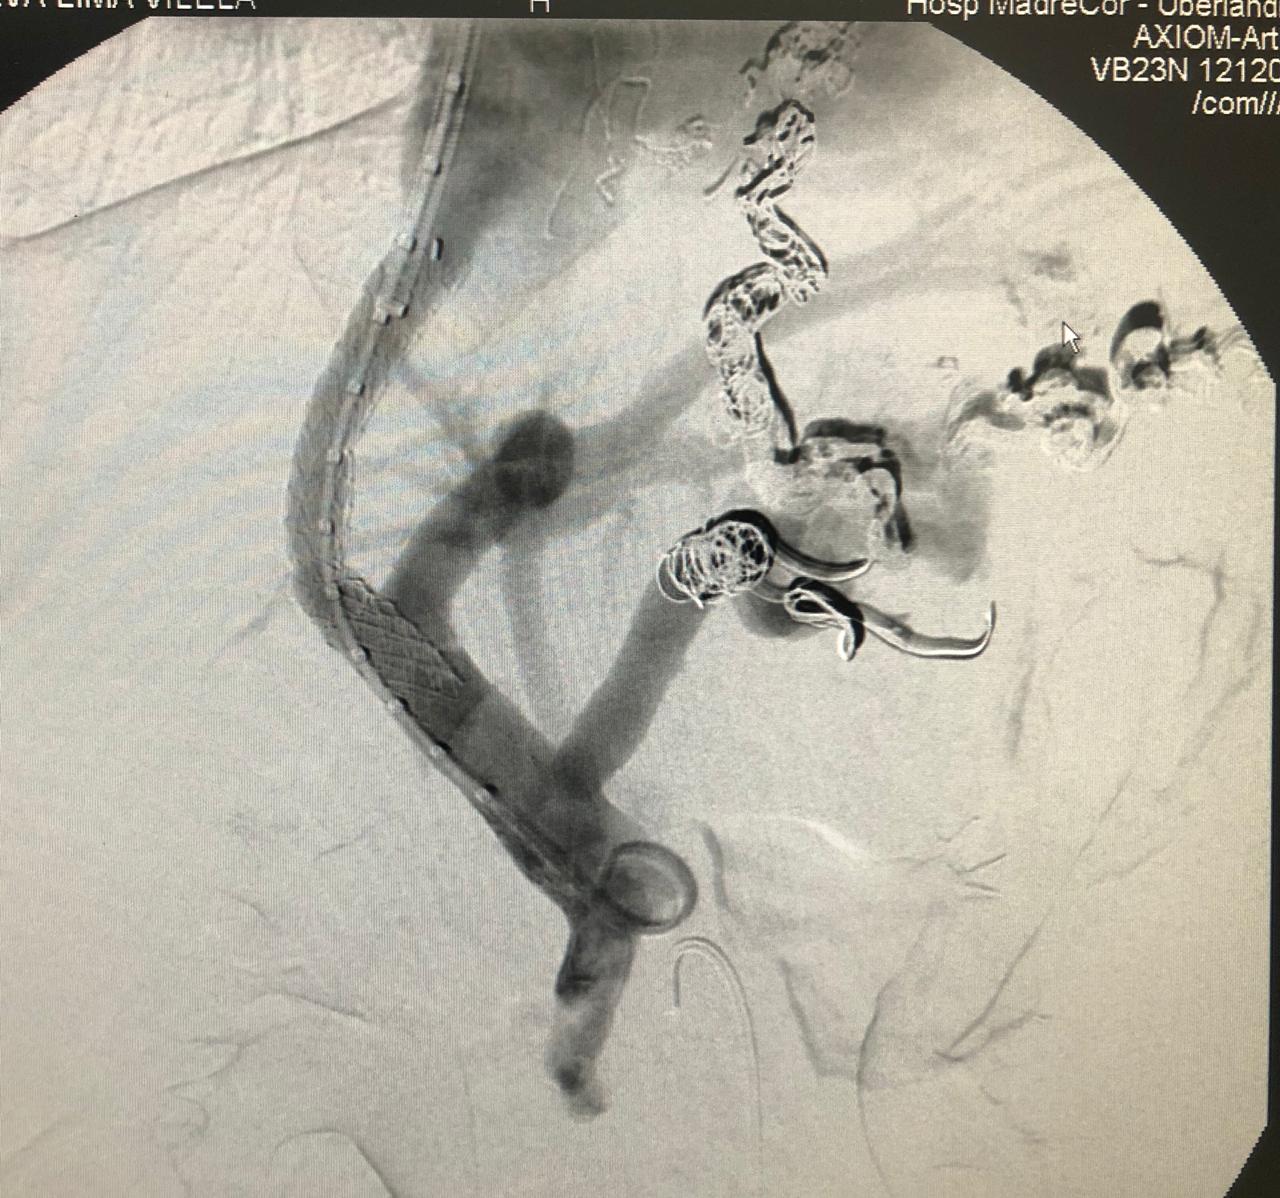

A cidade de Uberlândia-MG registrou uma cirurgia de alta complexidade inédita, neste mês, realizada no Madrecor Hospital. Denominado Transjugular Intrahepatic Porto-Systemic Shunt (TIPS), no português traduzido como Derivação Portossistêmico Intra-hepático Transjugular, o procedimento é da especialidade da radiologia intervencionista, que significa a implantação de um canal artificial (shunt) no fígado que estabelece comunicação entre a veia portal de entrada e a veia hepática de saída, em pacientes com fígado cirrótico.

A radiologia intervencionista é uma especialidade médica que atua em procedimentos minimamente invasivos através de punções vasculares ou de órgãos. A especialidade tem interface com várias áreas da medicina dentre elas a gastroenterologia e hepatologia. “A indicação do procedimento de TIPS nesta paciente era uma maneira de reduzir a probabilidade de novos episódios de sangramento, pois fazendo o desvio (shunt) por dentro do fígado, a pressão nas varizes de esôfago seria menor, consequentemente, minimizaria a chance de hemorragias”, relata Dr. Túlio Leite, radiologista intervencionista responsável pelo procedimento.